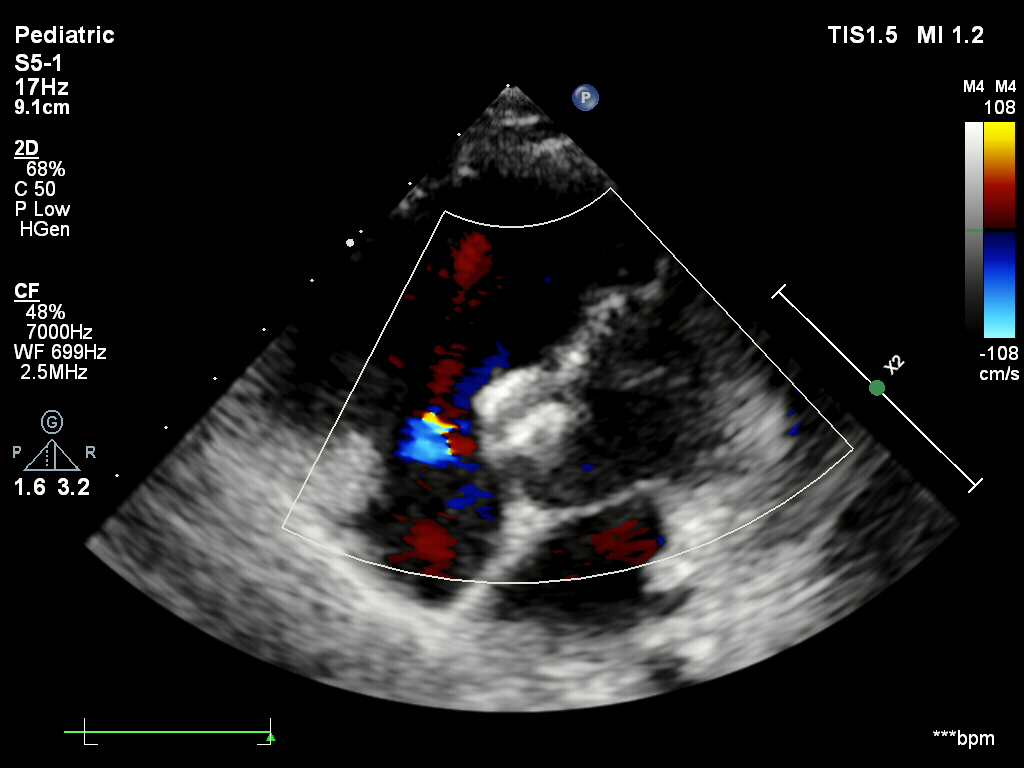

超声下确认封堵器位置正确

骑跨于室间隔两侧

释放封堵器后,超声下观察封堵器形态良好

无残余分流,封堵成功